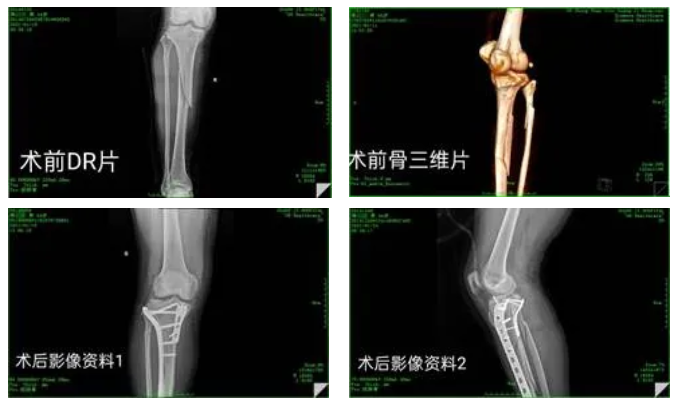

病例一:患者为44岁男性,因摔伤致右小腿肿痛活动受限1小时由急诊入院,结合X线检查及症状、查体,诊断为:右胫骨平台粉碎性骨折;右腓骨上段粉碎性骨折;右胫骨髁间棘撕脱性骨折;右后踝骨折;右膝前交叉韧带损伤;右膝外侧副韧带撕裂。患者入院后完善相关检查,针对其身体状况、年龄因素、愈后功能判断及对生活的影响程度综合分析,医院骨科组织讨论后决定,先进行胫骨中上段、胫骨平台骨折复位内固定手术,后进行关节镜检查、关节清理、半月板成形、髁间棘骨折复位内固定手术。

1611820883217787.png

杨述华教授对于此次查房的三个患者病例给出了专业的指导意见:病例一患者的手术复位效果良好,胫骨平台骨折治疗不当容易引起创伤性关节炎,一定要及时指导患者功能锻炼;病例二患者手术选择时机及时有效,术式合理,需要加强石膏托固定塑性;病例三患者颈5椎体血管瘤的情况需要密切观察、每半年进行一次MRI复查,必要时行PVP手术。